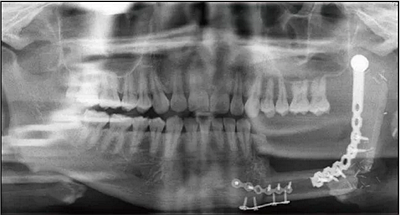

2014年6月9日于本院行下頜骨左側(cè)成釉細(xì)胞瘤切除術(shù)+下頜骨節(jié)段性切除術(shù)+重建板重建術(shù)+血管化腓骨肌皮瓣轉(zhuǎn)移修復(fù)術(shù)+鈦板內(nèi)固定術(shù)+血管吻合術(shù)+牽引釘植入術(shù)+拔牙術(shù)(圖2)。

2016年3月22日復(fù)查,全景片示34~37牙缺失,左下頜單層腓骨移植,腓骨與下頜骨對接處骨愈合良好,鈦板鈦釘在位(圖3)。